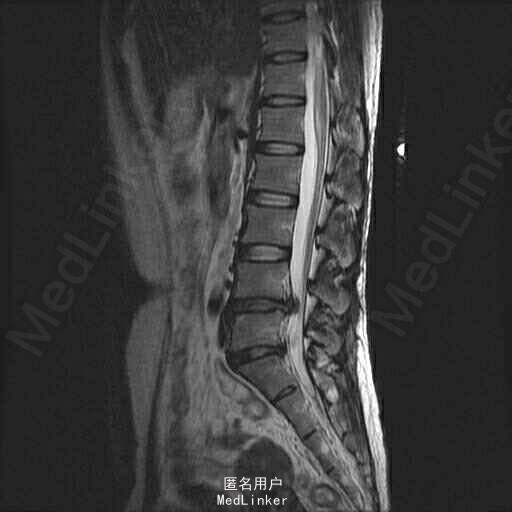

主诉:左下肢疼痛伴腰痛1月 病史:患者女性,39岁,十月前无明显原因发生腰痛,休息后缓解。未做其他治疗,1月前,出现左腿放射性疼痛,外侧及足后为主,腰部酸胀,无麻木等异常感,腰部活动障碍,不能正常行走,发病来大小便正常。在外院行ct检查后,诊断为腰椎间盘突出,未见影像片。

查体:脊柱无侧弯,腰部叩痛,活动障碍。上肢肌力感觉均正常。左下肢疼痛伴稍麻木感,肌力可,跟膝腱反射正常,直腿抬高试验:左侧55度,右侧35度,病理征未引出。 辅助检查:x线见腰椎退行性改变 MRI:L4-5,L5-S1椎间盘突出

诊断:L4-5,L5-S1椎间盘突出 治疗;患者神经压迫症状是由L4-5节段椎间盘突出所致,手术主要对L4-5节段减压,后固定。